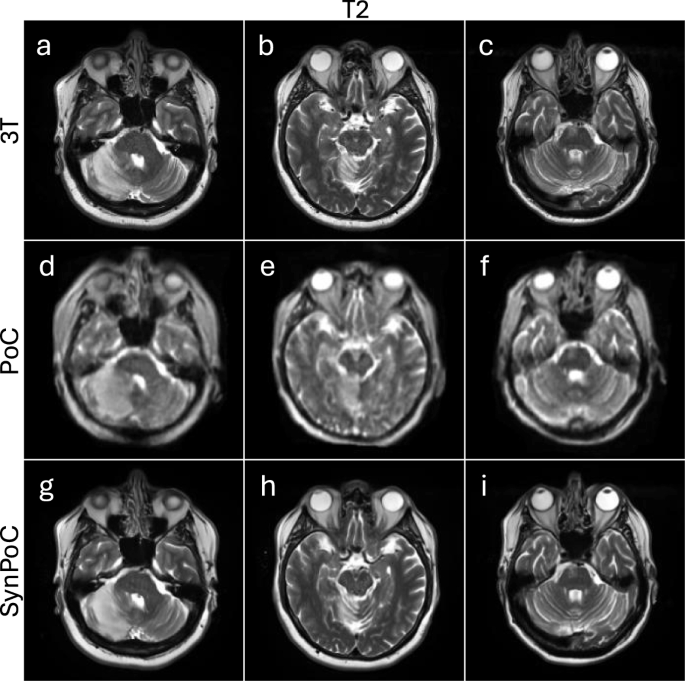

Figure 6 shows three patients with acute ischaemic infarcts in different brain regions, a male in his early 70s diagnosed with a large middle cerebral artery cerebral infarct, a male patient in his late 60s diagnosed with an acute right superior cerebellar artery infarct and a male patient in his late 60s diagnosed with a right pontine brainstem infarct (Fig. 6). Figure 6a–c display 3T T2-weighted images providing high-resolution visualization of the infarcted area. These images capture detailed morphological features, including the extent of the infarct and associated edema, which are crucial for accurate diagnosis and management of ischemic stroke.

The ULF MRI images (Fig. 6d–f) identify the presence of the infarct but with diminished signal, resolution and contrast. The boundaries of the infarct are less defined and in smaller infarcts, the lower SNR may contribute to diagnostic error. The SynPoC images (Fig. 6g–i) exhibit improvements in visual quality, enhancing infarct visibility and more closely approximating the clarity and structure seen in 3T MRI images. These visual enhancements suggest that SynPoC may recover structural detail less apparent in native PoC images; however, caution is required when interpreting synthetic images in a diagnostic context. This visual trend was observed across infarcts of varying sizes, but further validation is needed to confirm generalizability.